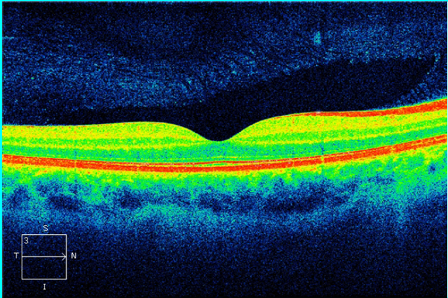

Já a Tomografia de Coerência Óptica ( OCT) é um exame diagnóstico parecido com um ultrassom, que utiliza luz no lugar do som. O exame é não invasivo, não havendo contato com o olho, também indolor. Neste exame é possível verificar a mácula, se está preservada, conforme a foto abaixo.